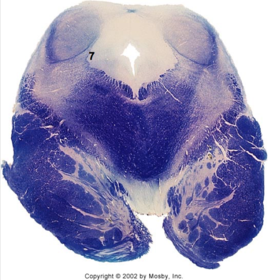

| CN IX | |

| Inferior cerebellar peduncle | |

| Inferior olivary complex | |

| Dorsal cochlear nucleus | |

| Inferior vestibular nucleus | |

| Medial vestibular nucleus | |

| Spinal nucleus of V | |

| Spinal tract of V | |

| Medullary pyramids | |

| Solitary nucleus | |

| ALS | |

| Medial lemniscus | |

| Medial longitudinal fasciculus | |

| Ventral cochlear nucleus | |

| Anterior spinocerebellar tract | |

| Central tegmental tract | |

| Olivary internal arcuate fibers | |

| Solitary tract | |

| Abducens root fibers | |